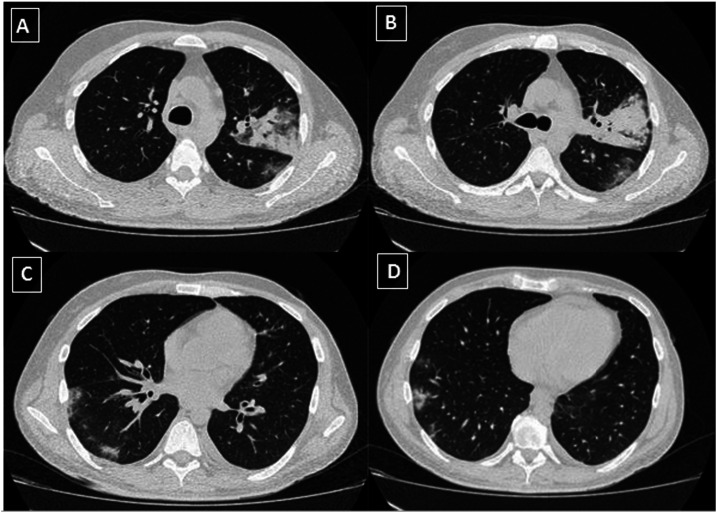

Chest CT revealed bilateral glass-ground opacities occupying approximately 25% of both lungs (Figure 2A–D). Respiratory secretion was collected with a nasopharyngeal swab and tested positive for SARS-CoV-2. Mycobacterium tuberculosis DNA was detected using PCR (GeneXpert MTB/RIF assay) without RIF resistance. Treatment was initiated with azithromycin (500 mg/day), HCQ (400 mg/day) for 5 days, and ceftriaxone (2 g/day). He was treated with isoniazid, ethambutol, pyrazinamide, and RIF. Antiretroviral therapy was not started to avoid complications with anti-TB treatment. The patient was clinically stable and discharged to home after 1 week. Currently, the patient is under follow-up and remains asymptomatic without developing relapses.

Figure 2.

Chest computed tomography (CT). (A and B) Axial thin-section unenhanced CT image revealing consolidative pulmonary opacities in the left upper lobe. (C and D) Axial thin-section unenhanced CT image showing multifocal, rounded, and bilateral ground-glass opacities, with peripheral and posterior predominance in the right lower lobe.